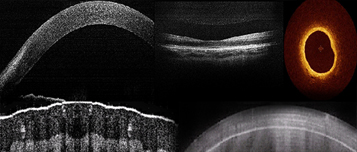

各种光学相干成像(OCT)系统开发

- 可定制各种时域、频域和扫频OCT系统(optical Coherence

Tomography)。工作波长:1310nm、850nm、1060nm等。

应用场合:眼底成像、眼前节成像、皮肤成像、血管内窥、胃肠

食道内窥、珠宝文物鉴定、检疫、基因检测等场合。